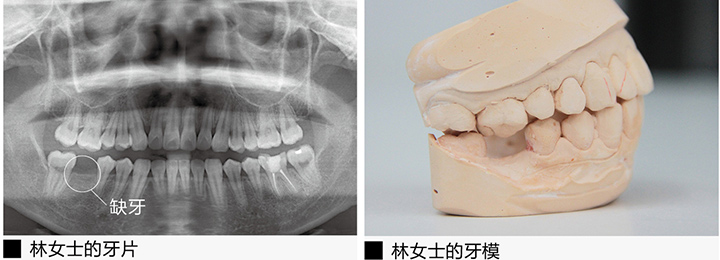

林女士的“六龄齿”也就是第一恒磨牙,缺失了整整5年了,从一开始的蛀牙没有及时补起来,到后来不断地塞牙发炎,蛀洞变大,到最后整颗牙掉落,林女士没少受罪。对于看牙,她害怕得很。补牙,拔牙都怕,更别说在那么窄小的牙槽骨里植入种植体,进行种植牙修复了。

可是,一想到自己年纪还轻,嘴里的其他牙齿也多少有龋坏,缺损等各种问题,如果这颗牙再不修复,不仅增加了其他牙齿的咀嚼负担,缺牙边上的牙齿也会因为没有依傍而倾斜,林女士想要用种植牙让自己的“六龄齿”重生起来。

可是种植体那么小,只有几个毫米,牙骨也那么狭窄,我们的口腔内又有着十分细小的神经,医生真的能把那么微小的种植牙做到高精和安全吗?直到亲眼见证了美奥口腔的显微口腔治疗,看到放大30倍后的清晰口腔视野后林女士才放下心来,决定进行种植牙治疗。